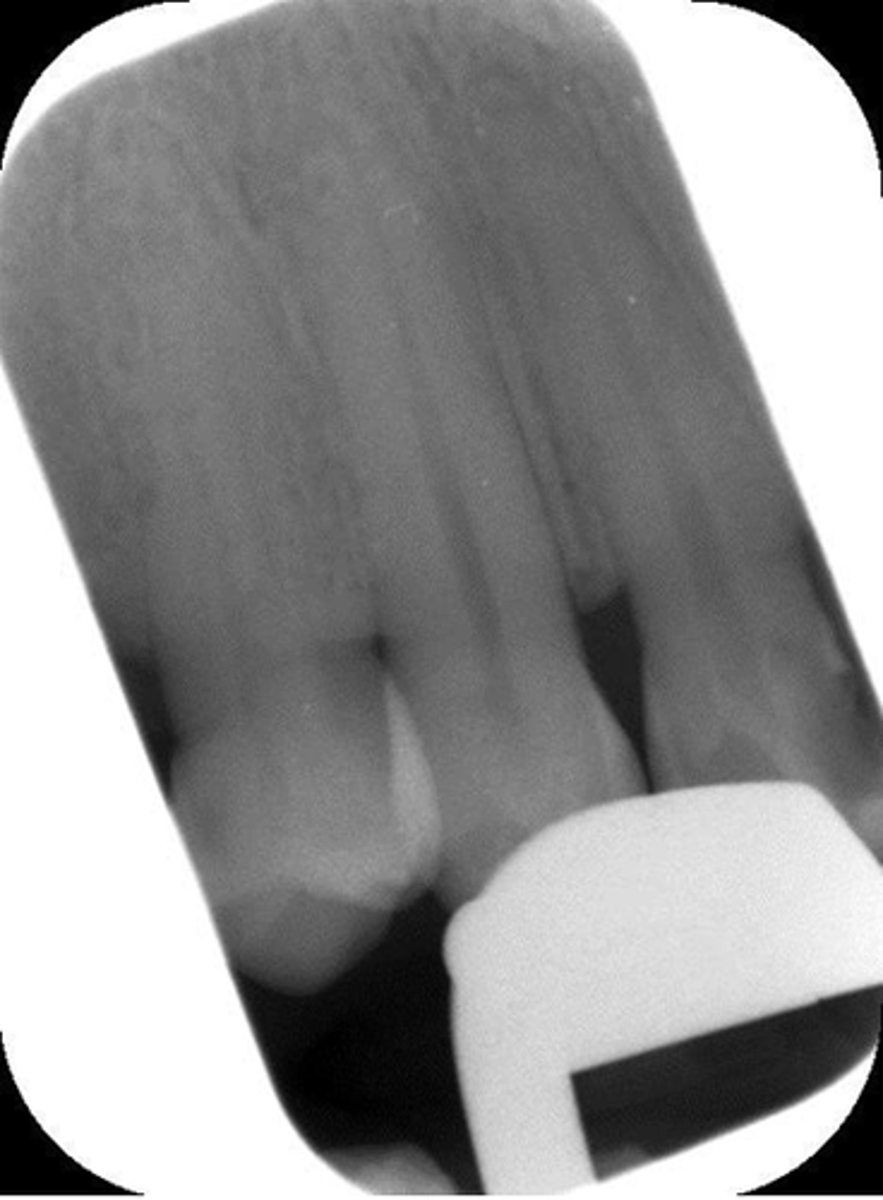

Rinn instrument bar, vertical angulation

What is this error?